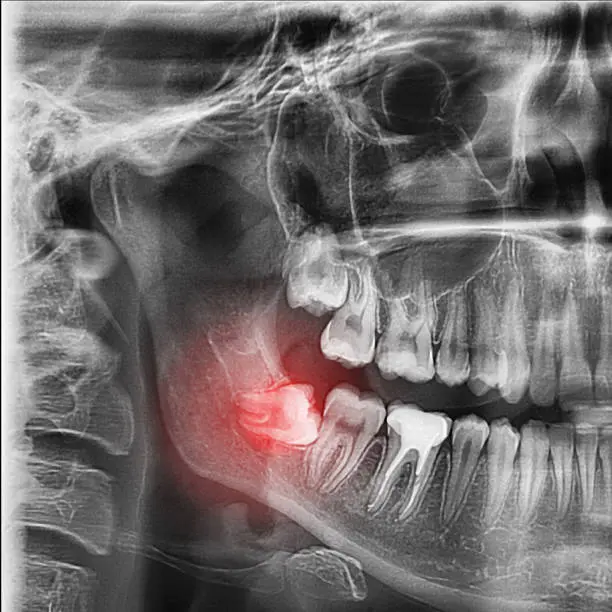

ฟันคุดคือ ฟันกรามซี่ในสุด ทั้งหมด 4 ซี่ บน ล่าง ซ้าย ขวา ไม่สามารถขึ้นได้ตามปกติเพราะพื้นที่ไม่เพียงพอให้ฟันสามารถขึ้นมาได้ บางซี่อาจจะโผล่ขึ้นมาเล็กน้อย และบางซี่ถูกฝั่งอยู่ในกระดูดขากรรไกร อาจจะขึ้นตรง เอียงหรือนอนในแนวราบส่วนใหญ่ฟันคุดมักพบว่าอยู่ที่ฟันกรามซี่ล่างในสุดและพบมากสุดในช่วงอายุ ประมาณ 16 – 25 ปี หรืออาจจะช้ากว่านั้น